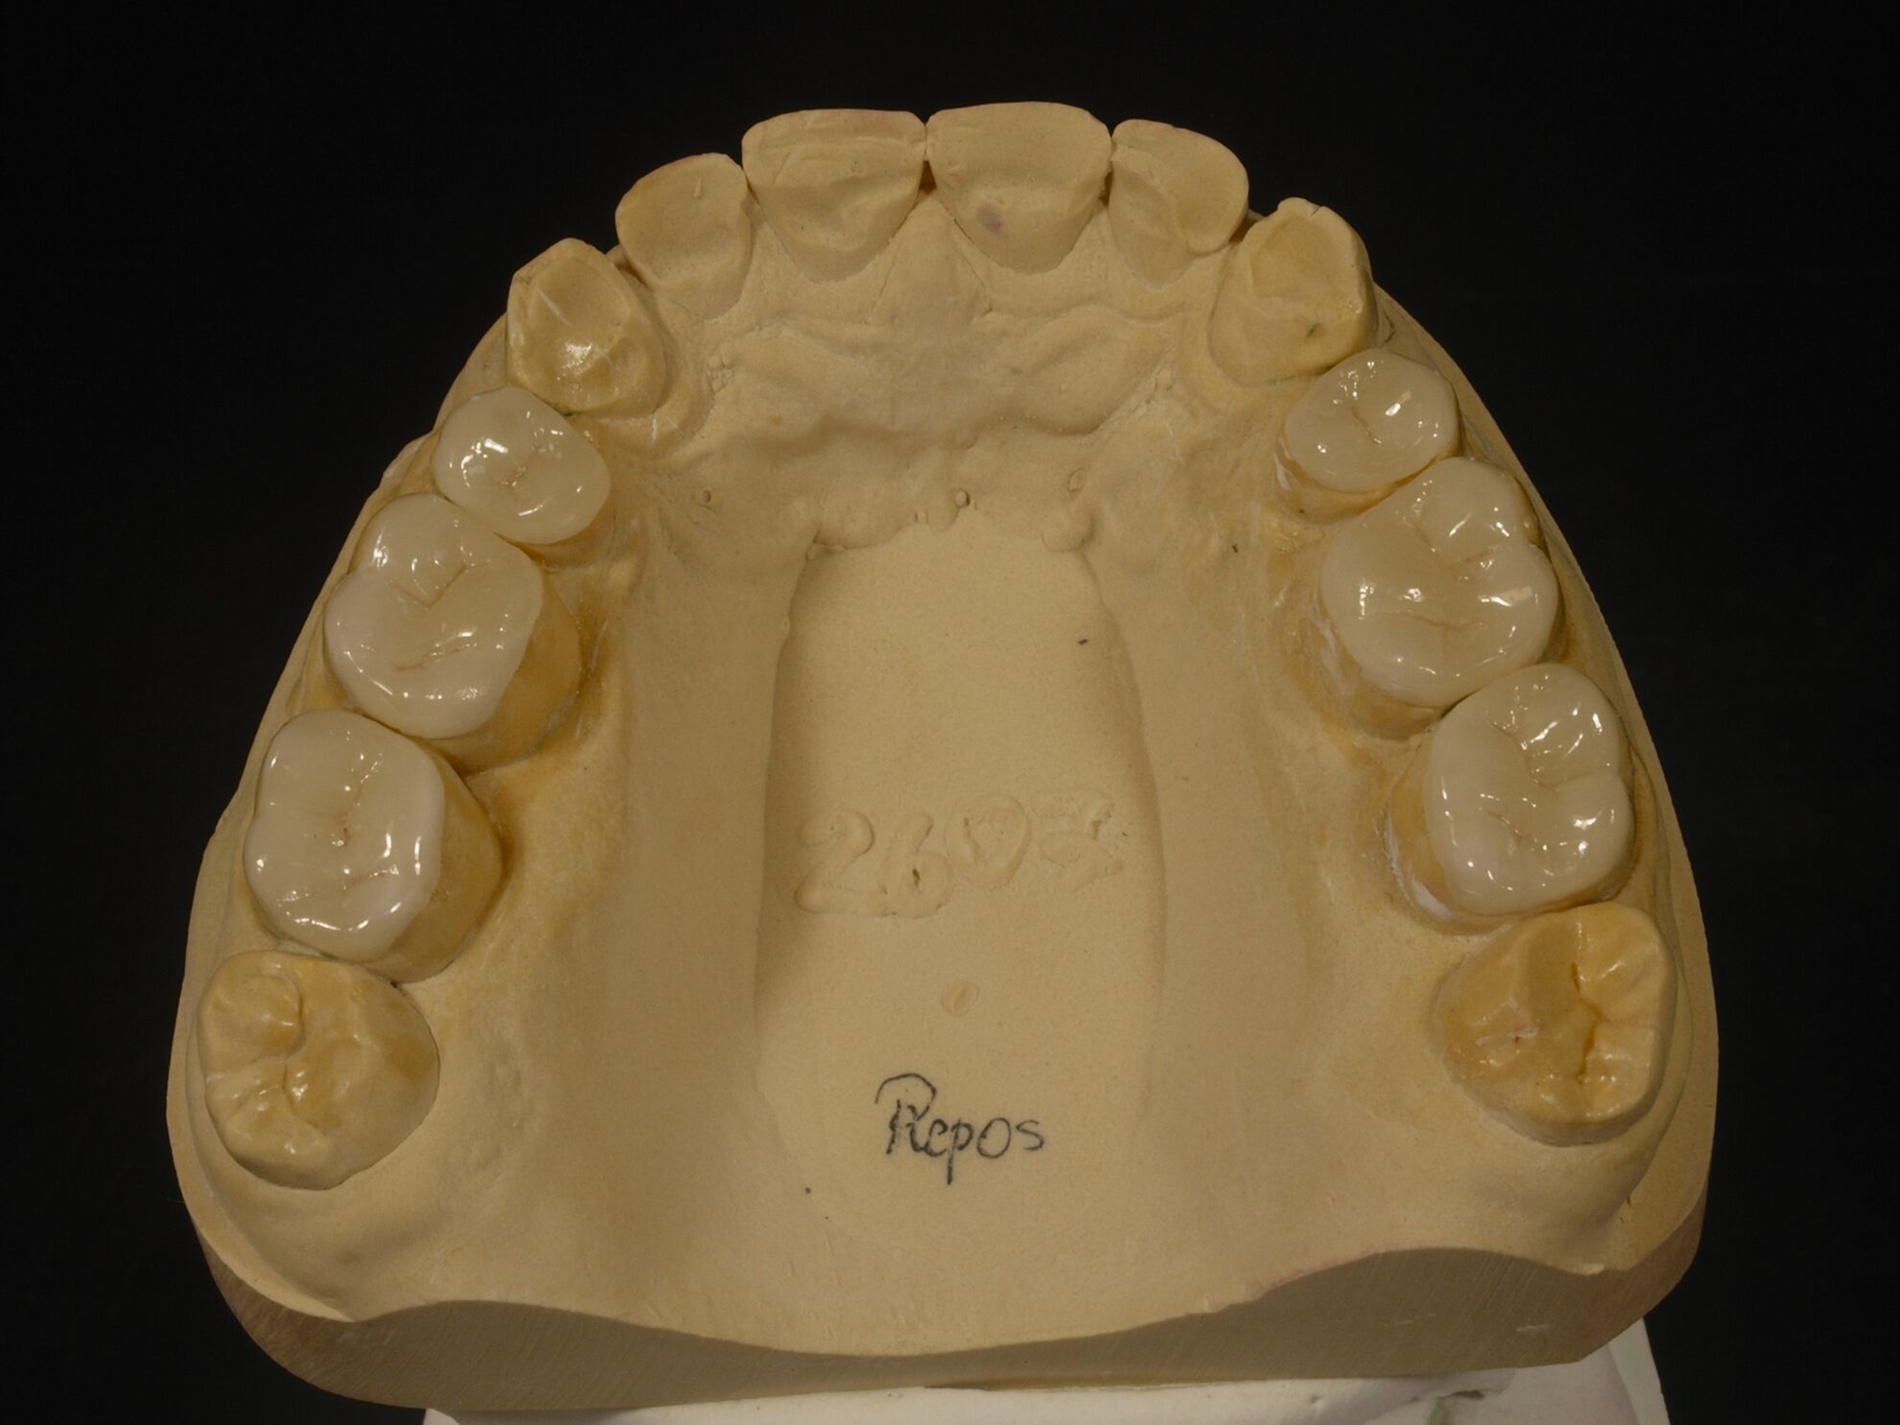

Auch erheblicher Zahnverschleiß lässt sich theoretisch mittels intraoral direkt verarbeiteter Komposit-Restaurationen behandeln. Dies erfordert dann allerdings zusätzlichen erheblichen zahntechnischen Vorbereitungsaufwand. An dessen Anfang stehen indirekte Präzisionsabformungen, die darauf beruhende Herstellung von Kiefermodellen und Duplikaten aus Superhartgips, deren schädelbezügliche Montage im Artikulator wegen der nachfolgenden Änderung der vertikalen Dimension.

Die Position des Unterkiefermodells wird zumeist auf der Grundlage von Registraten festgelegt. Die AWMF-Leitlinie zur instrumentellen Funktionsanalyse der DGFDT [Utz et al., 2022] empfiehlt, bei funktionsgesunden Patienten, die bei natürlicher Bezahnung in maximaler Interkuspidation gut abgestützt sind, diese Unterkieferposition in der Regel zu übernehmen (Empfehlung 25). Anders ist es, wenn zu wenige interokklusal abstützende Zähne vorhanden sind, eine sekundäre Unterkieferverlagerung vorliegt – etwa durch Zahnverschleiß – oder der Kauflächenkomplex insgesamt restauriert werden muss; in diesen Fällen sollte die vorliegende habituelle Okklusion in die restaurative Behandlung nicht übernommen werden. „In diesen Fällen hat sich die zentrische Kondylenposition, die dann zur zentrischen Okklusion wird, als Referenzlage bewährt (Empfehlung 26).“

Diese Simulation der Okklusion bildet die Voraussetzung für das nachfolgende Wax-Up der geplanten Zahnform als zahntechnische Planungsgrundlage. Das so ergänzte Kiefermodell wird anschließend dubliert, als Grundlage der Herstellung neuer Kiefermodelle in neuer Kontur, auf denen wiederum speziell verstärkte Formteile für die spätere intraorale Ausformung der Komposite erstellt werden. Die Ausformung der Restaurationen aus Kompositen und ihre Aushärtung erfolgen insofern zwar intraoral „direkt“, das Gesamtvorgehen ist aber an die gleichen zahntechnischen Vorarbeiten gebunden wie eine Therapie mittels indirekter Restaurationen. Solchermaßen hergestellte Restaurationen überstehen nach Untersuchungen der engagierten Kollegen aus Zürich drei Jahre in gutem Zustand [Schmidlin et al., 2009]; nach fünf Jahren ist der Zustand allerdings beeinträchtigt [Attin et al., 2012].

Für die Behandlungsabfolge bestehen verschiedene Möglichkeiten, die unmittelbar mit der Kontrolle der Gelenkstellung verbunden sind. Generalisierter Zahnverschleiß erfordert häufig eine Behandlung aller Zähne zumindest eines Kiefers, weil der vertikale Platzbedarf zum Schutz der geschädigten Zähne eine Erhöhung der vertikalen Dimension erfordert. Dies bedingt insofern eine zeitgleiche Versorgung aller behandelten Zähne zumindest im Seitenzahnbereich, weil sonst eine ungleichmäßige Abstützung resultiert. Bewährt hat sich die Aufteilung derartig aufwendiger Behandlungen in mehrere Abschnitte. Dabei erfolgt im ersten Abschnitt die Abstützung im Seitenzahnbereich in neuer VD, in der Regel einhergehend mit einer semipermanenten Versorgung der Frontzähne zur Wiederherstellung der dynamischen Führung in neuer VD. Im begründeten Ausnahmefall kann dieser Schritt entfallen, etwa bei unmittelbar nachfolgend geplanter Behandlung der Frontzähne; in dem Fall erfolgt die Steuerung der dynamischen Okklusion in der Zwischenzeit mit einer entsprechend gestalteten Okklusionsschiene, die auch tagsüber getragen wird (Abbildung 11).